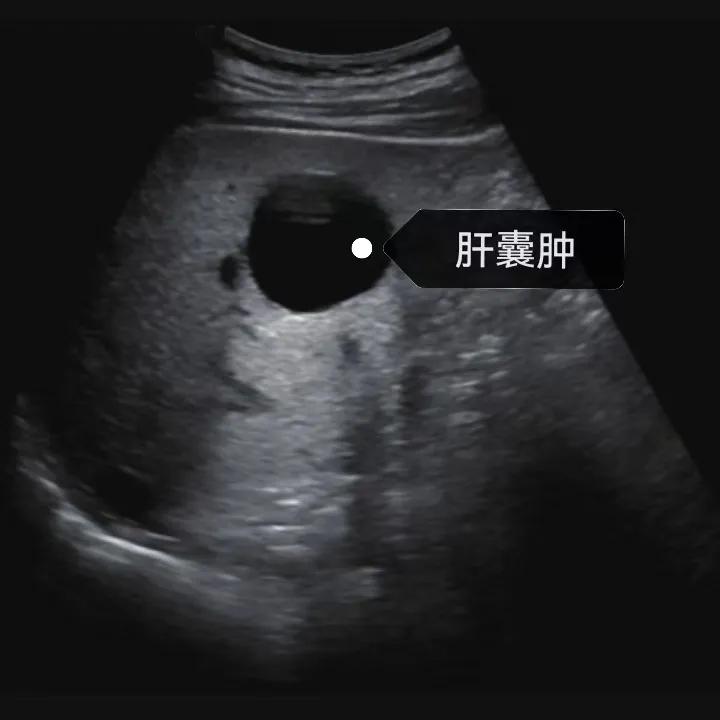

肝囊腫是一種常見的肝臟良性疾病,呈圓形或橢圓形,外由上皮細(xì)胞包裹形成包膜,內(nèi)由清亮、無色、無細(xì)胞成分的囊液填充,看上去就像是一顆注滿了水的氣球,因此通俗一點(diǎn)說就是肝臟中的“水泡”。

超聲通常是診斷肝囊腫的首選方法,彩超對(duì)肝囊腫的檢出率可達(dá)98%,<1cm的囊腫也可檢出。肝囊腫常表現(xiàn)為圓形或橢圓形無回聲,包膜光滑完整,邊界清晰,可有側(cè)壁回聲失落征象,后方回聲增強(qiáng)。病程長(zhǎng)、囊腫較大者或囊內(nèi)有過出血、感染者,無回聲腔內(nèi)可見少量絮狀回聲漂浮。超聲對(duì)肝囊腫的診斷準(zhǔn)確而靈敏,且方法簡(jiǎn)單、無創(chuàng)、費(fèi)用低、可重復(fù)性高,因此常常被作為首選。